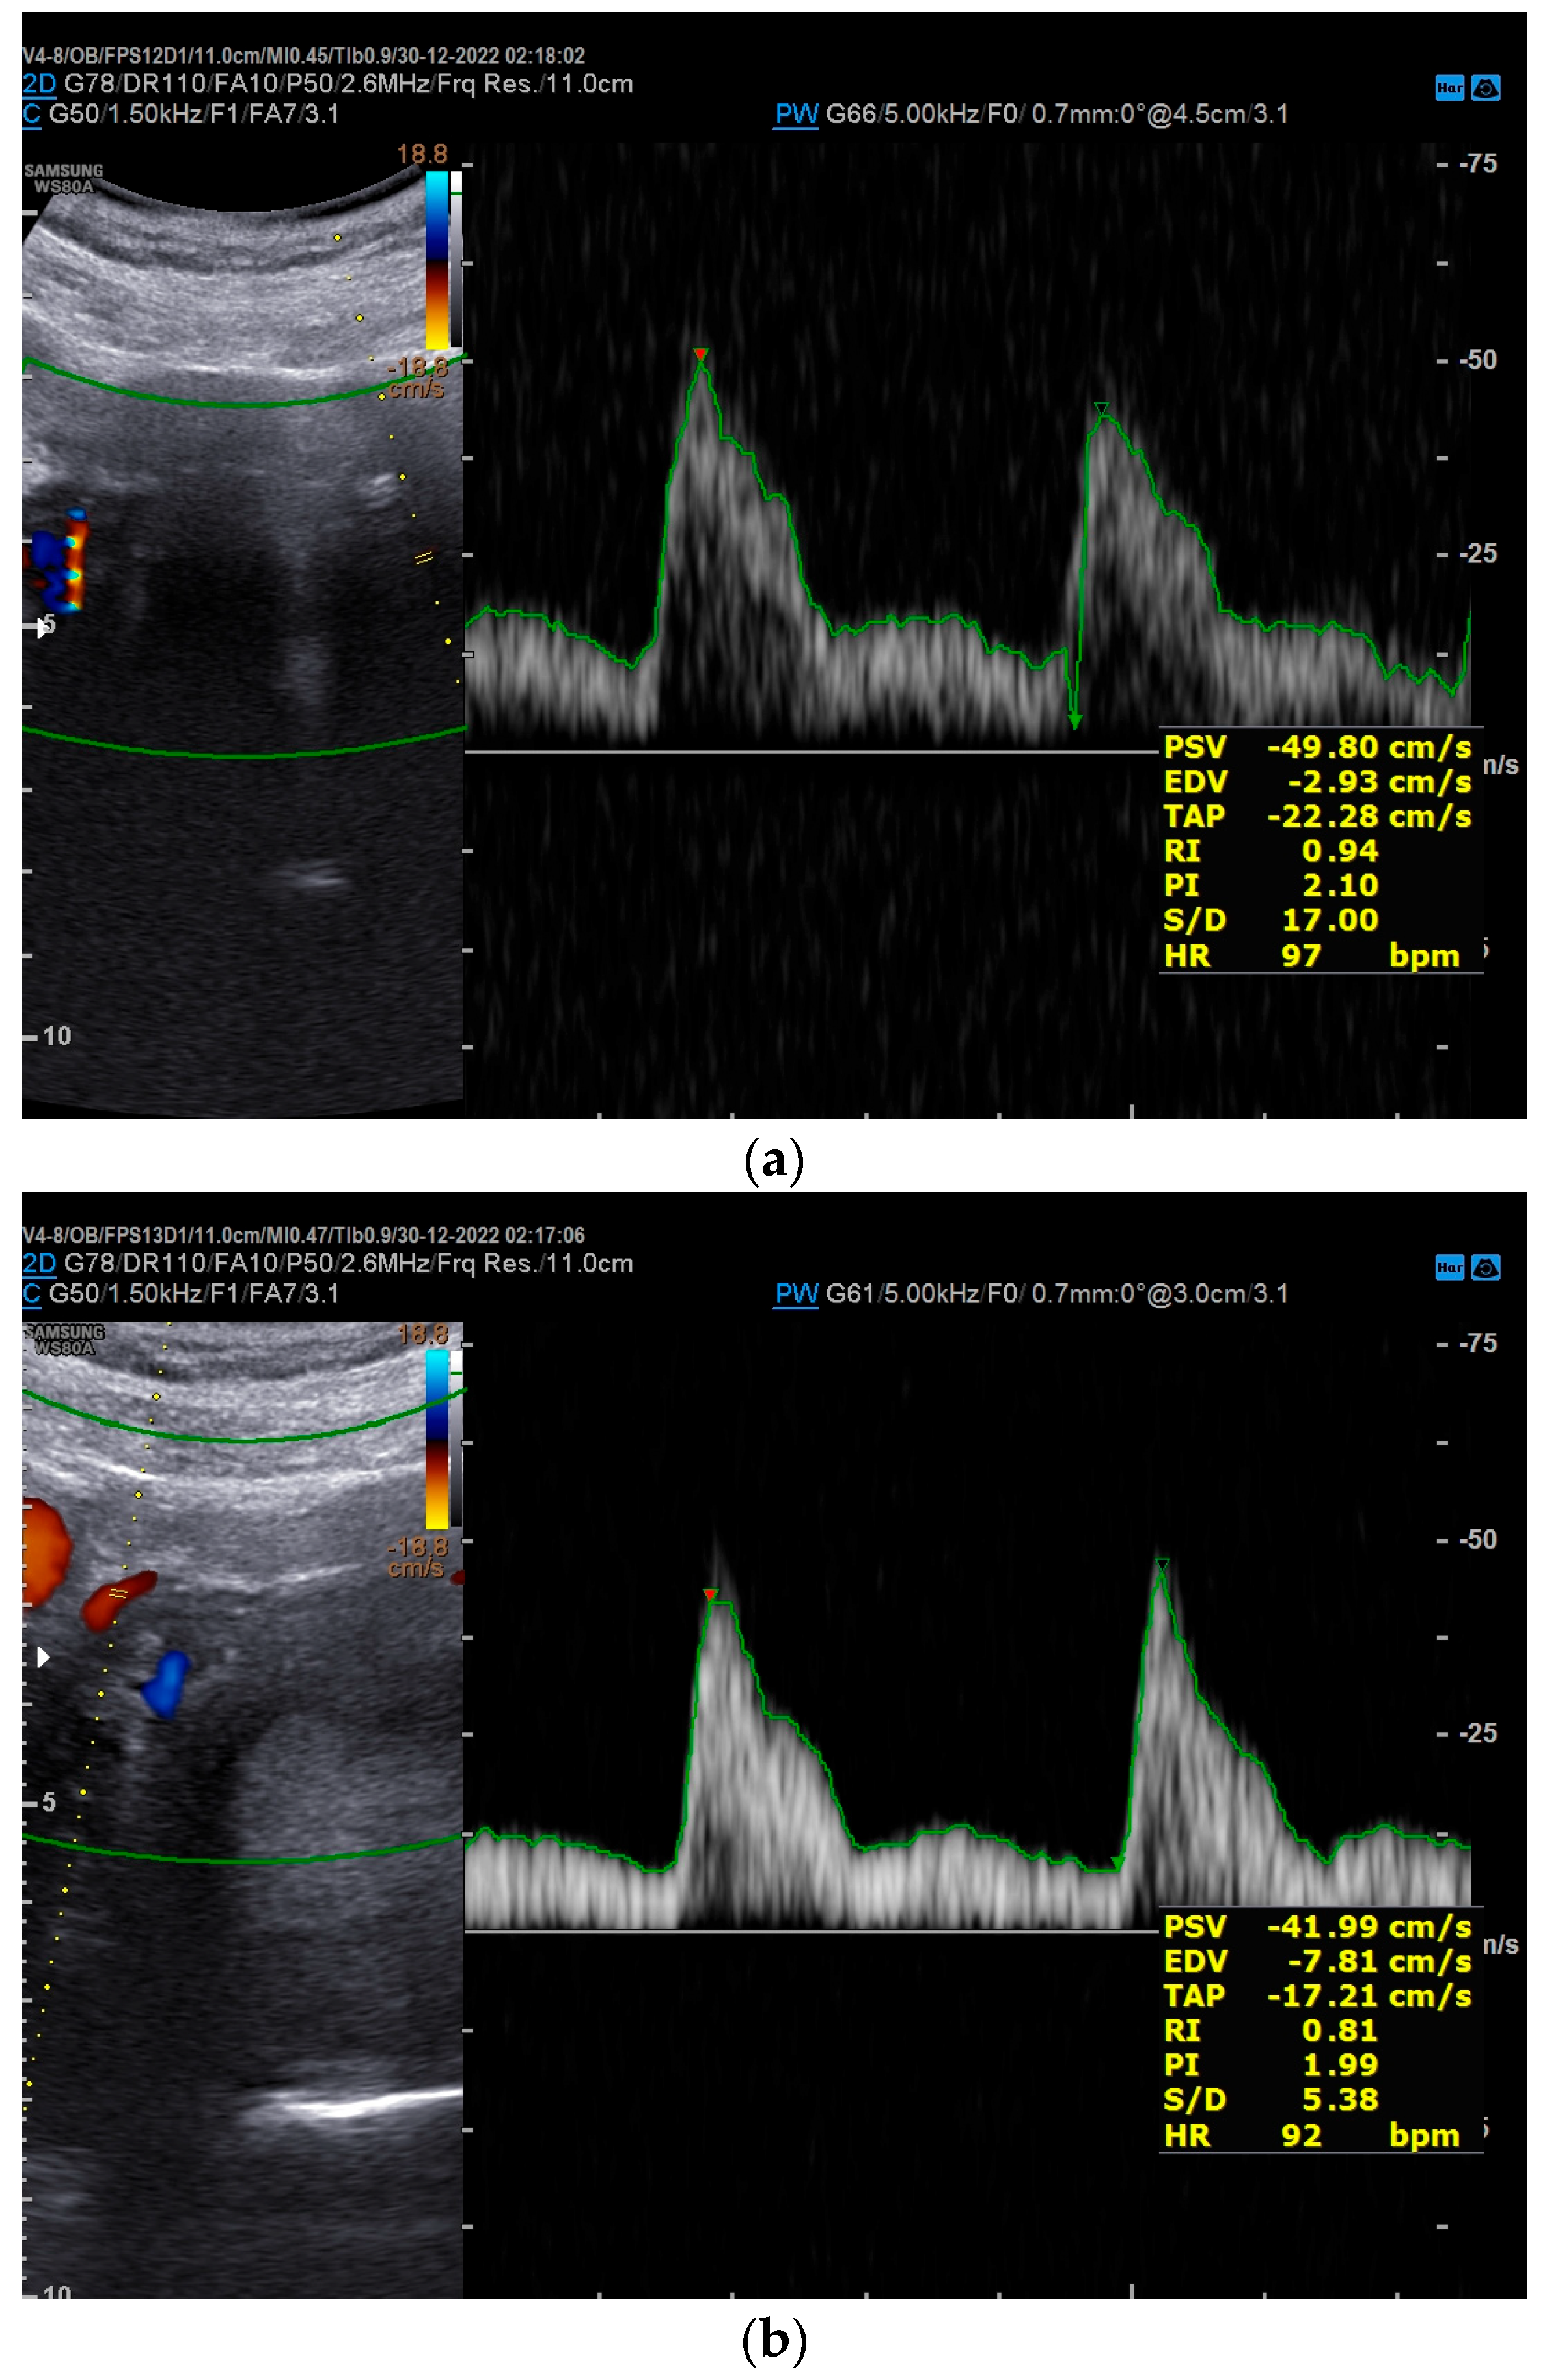

2. Case Presentation